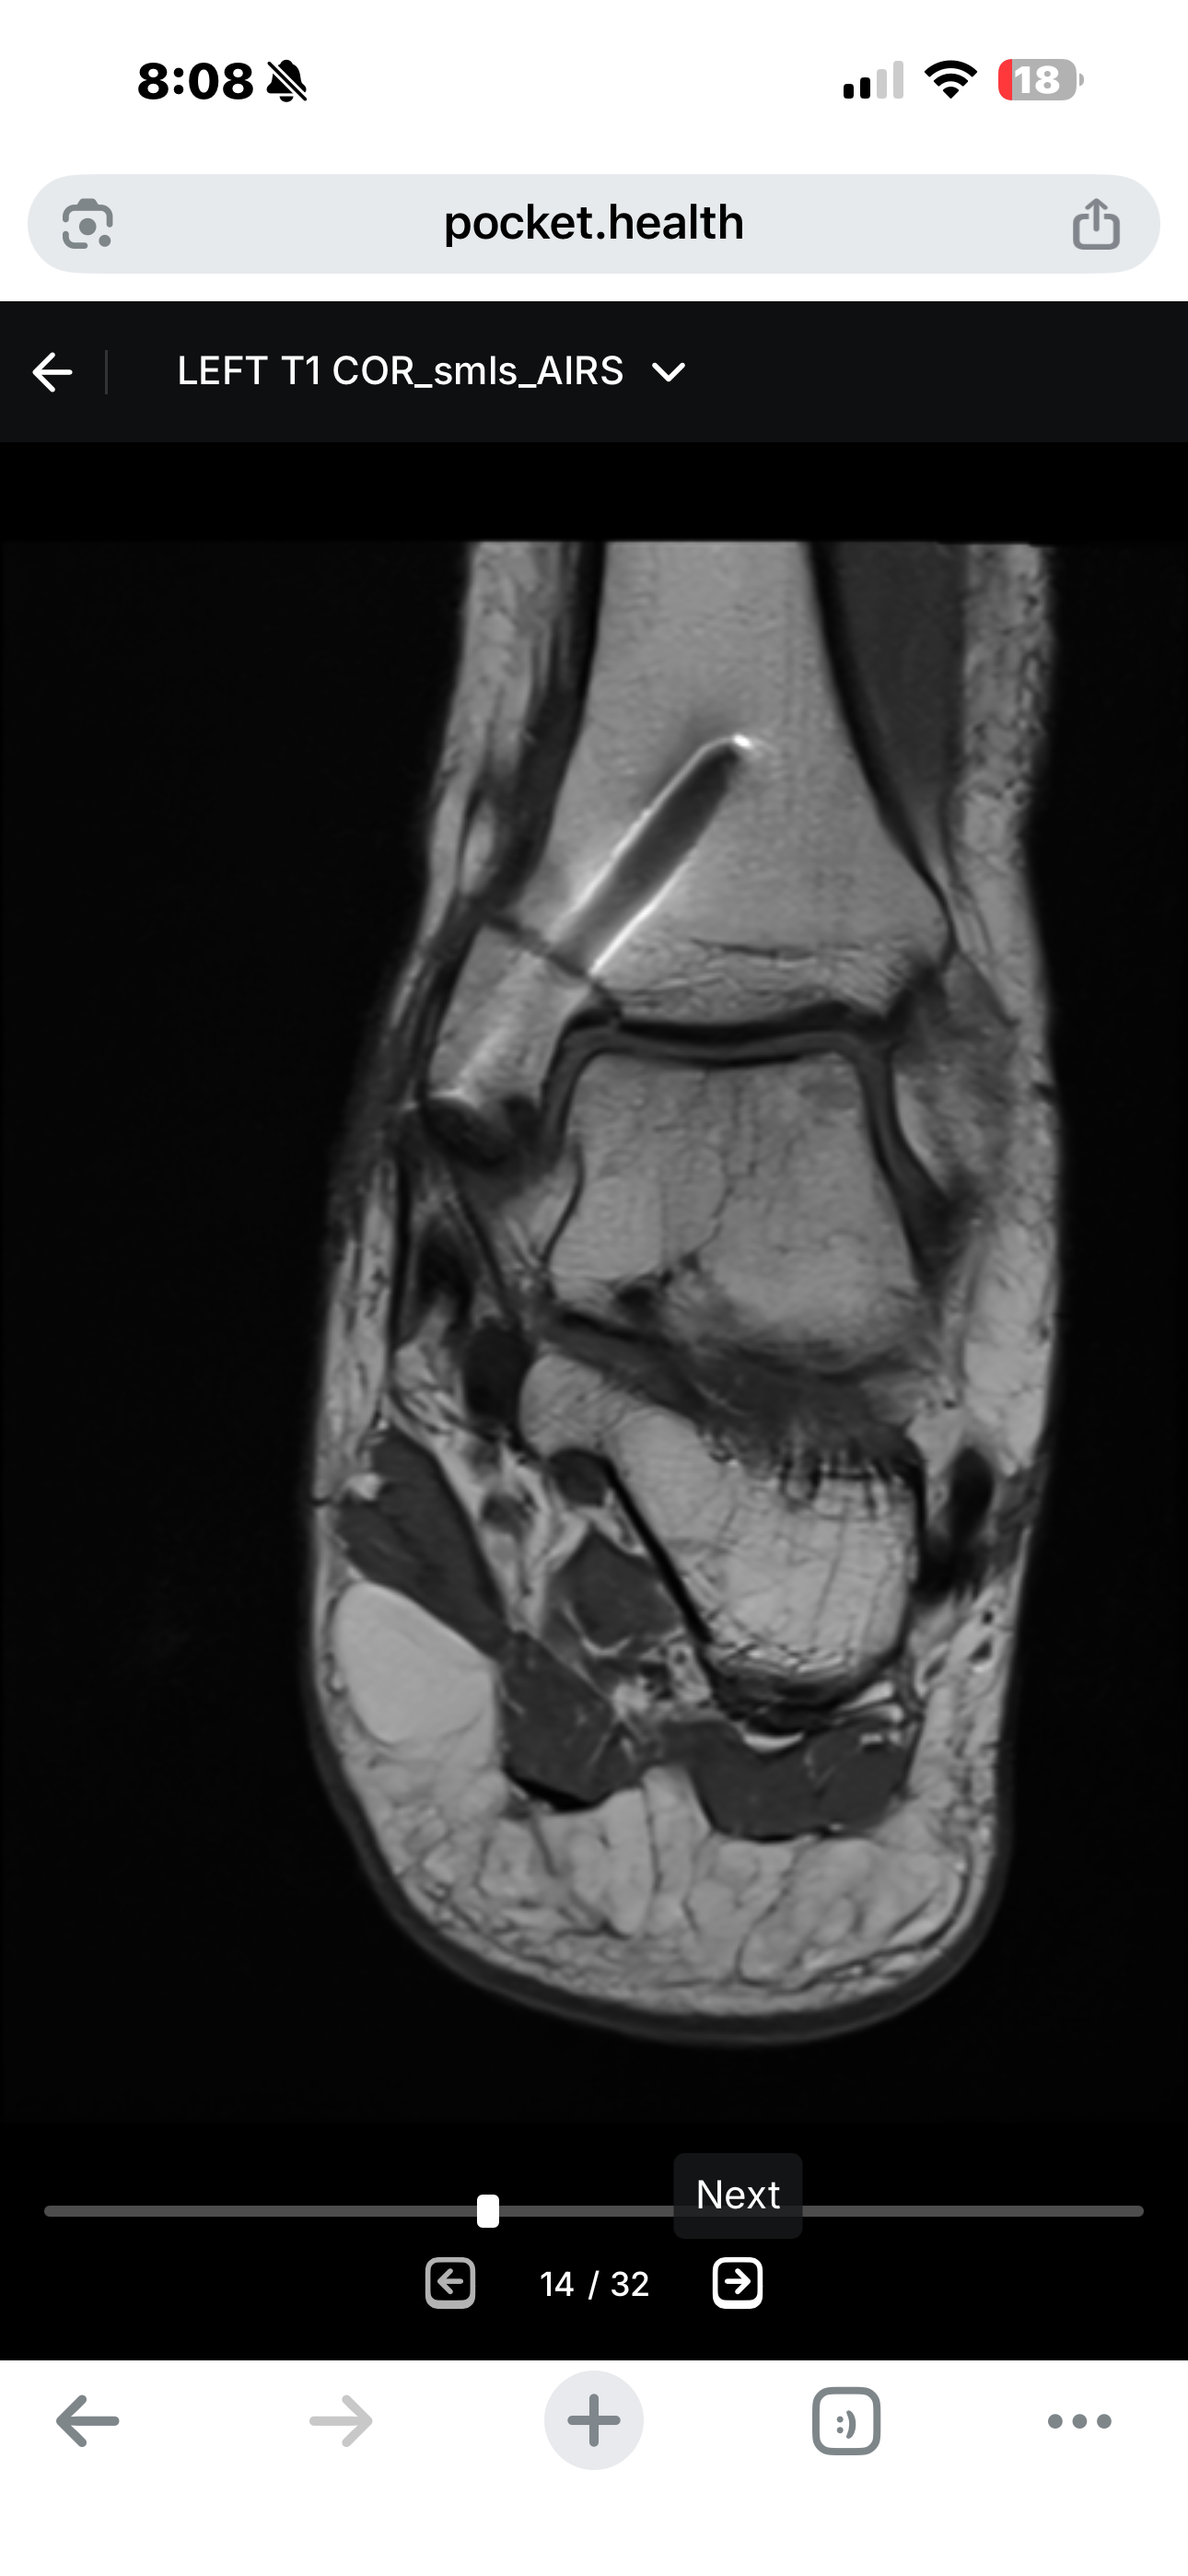

En mayo de 2025, mientras trabajaba, un elevador de tijera de 3,200 libras se descontroló y pasó por encima de mi tobillo, aplastando y destrozando la parte baja de mi pierna. Ese día no solo se rompieron mis huesos, también se quebró mi independencia, mis sueños y la vida que conocía.

Sufrí fracturas múltiples, hemorragias internas y un daño nervioso tan severo que los médicos me diagnosticaron CRPS (Síndrome de Dolor Regional Complejo) — conocido como “la enfermedad más dolorosa del mundo”.

He pasado por cirugías, bloqueos nerviosos y largas estancias en hospitales. Hace tres semanas intentaron un procedimiento para aliviar el dolor, pero no funcionó. Ahora me aferro a mi última esperanza: un estimulador medular.

Para poder colocarlo tengo que someterme a una cirugía temporal, donde me lo prueban por unos días para ver si funciona. Si me ayuda, entonces me tendrán que hacer una segunda cirugía para dejarlo de manera permanente dentro de mi cuerpo. Sería como un marcapasos, pero para mi médula espinal: algo que podría darme la oportunidad de volver a caminar y, sobre todo, de volver a vivir con dignidad.

In May 2025, while working, a 3,200-pound scissor lift went out of control and rolled over my ankle, crushing and destroying the lower part of my leg. That day, not only were my bones broken, but also my independence, my dreams, and the life I once knew.

I suffered multiple fractures, internal bleeding, and severe nerve damage that led doctors to diagnose me with CRPS (Complex Regional Pain Syndrome) — known as “the most painful disease in the world.”

I have gone through surgeries, nerve blocks, and long hospital stays. Three weeks ago, I underwent a procedure hoping to relieve the pain, but it failed. Now my last hope is a spinal cord stimulator.

To receive it, I first need to undergo a trial surgery, where the device is temporarily placed in my body to see if it works. If it helps me, then I will need a second surgery to implant it permanently inside me. It would remain in my body like a pacemaker, but for my spine — something that could give me the chance to walk again and, more importantly, to live with dignity.